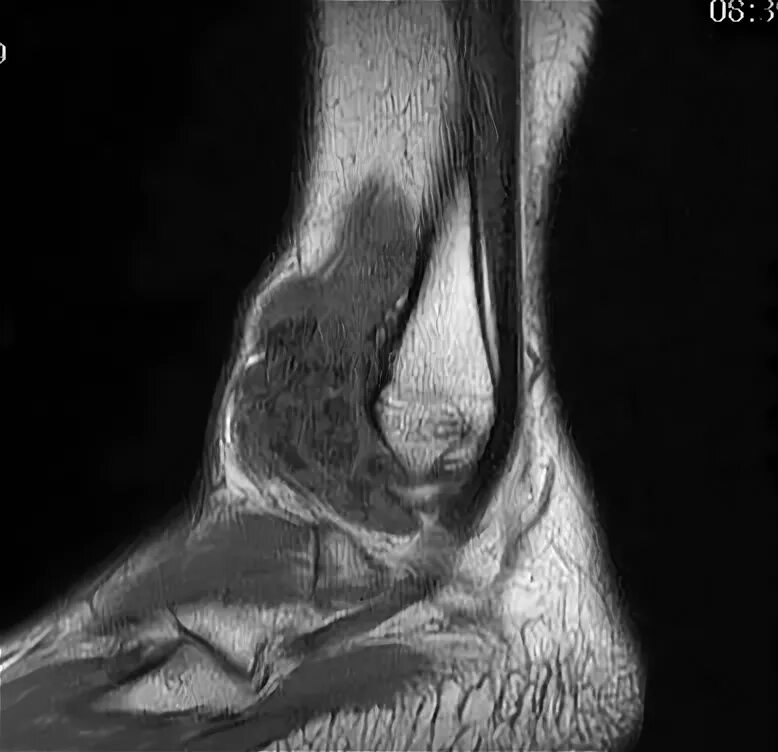

Пигментный виллонодулярный синовит